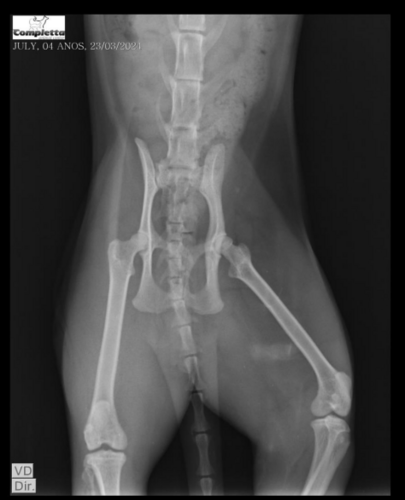

Minha gata foi atropelada ontem (22/03/24) e não prestaram socorro e as patas traseiras dela foram comprometidas (uma totalmente virada ao contrário) e será necessário realizar uma cirurgia para colocar a pata no lugar pois ainda a chance de salvar o membro, porém a cada dia que demoramos para pagar a cirurgia é um dia a menos que ela tem de conseguir manter as patas traseiras sem a necessidade de amputar.